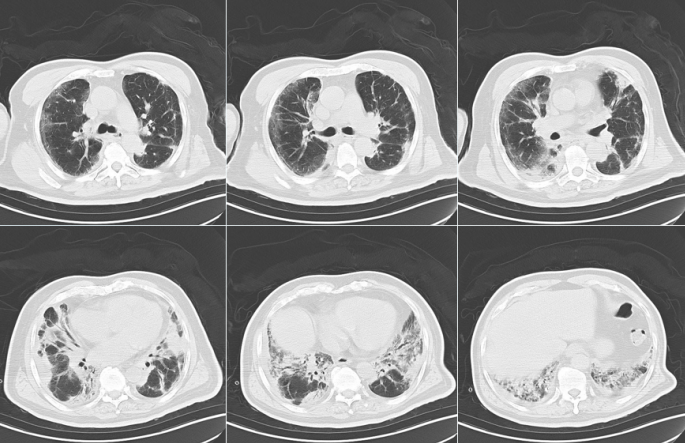

胸部CT(7月19日):胸膜下可见磨玻璃样渗出和斑片状实变影以及蜂窝状阴影,中下肺为著,呈间质性肺炎改变(图1)。

ASS-ILD患者HRCT表现在轴面分布特点以外周为主,冠状面主要在基底部分布,肺间质疾病的影像学类型以NSIP为主,其次是NSIP-OP。NSIP-OP是一种混合型ILD类型,即在NSIP背景上出现典型的OP,NSIP-OP的影像表现在其他ILD中相对少见,影像学表现NSIP-OP时,应寻找是否有抗合酶抗体的存在。

A:76岁女性,CT表现为双下肺为主的磨玻璃影、网格影,符合NSIP;B、C:同一患者46岁女性,B显示双肺下叶背段支气管血管束周围斑片状实变影,左侧呈反晕征,符合OP;C为稍下层面显示双肺下叶基底段磨玻璃影、网格影,符合NSIP,该患者影像表现为NSIP-OP;D:72岁女性,CT显示双下肺蜂窝影,符合UIP。ASS临床表现主要包括:肌炎、ILD、多关节炎、技工手、发热及雷诺现象。多项研究发现ILD是最常见的表现。特发性炎性肌病(IIM)患者中抗Jo-1抗体阳性ASS患者的关节炎发生率(64.2%)高于阴性者(18.1%)。ILD是ASS发病率和死亡率的主要决定因素。ASS-ILD可表现为ARDS和难治性呼吸衰竭,可于临床中任何时间发生。对于疑诊ILD,应使用HRCT和肺功能检查早期确诊。肺活检对明确ILD病因至关重要且可指导治疗。特发性炎性肌病常被分为多发性肌炎、皮肌炎和包涵体肌炎。大多数ASS患者既往会被分类为皮肌炎。10多年前只有少数肌炎包含相关的自身抗体,新的特异性自身抗原的发现成为此领域的一个重要进展,抗合成酶抗体(anti-synthetase antibody,ARS)阳性代表一种被称为抗合成酶综合征(ASS)的表型。抗组氨酰tRNA合成酶(JO-1)抗体(60%~80%)最为常见,其他还包括抗PL-7抗体(10%~15%)、抗PL-12抗体(5%~15%)、抗EJ抗体、抗OJ抗体(5%)、抗KS抗体、抗Zo抗体等。ASS治疗除治疗肌炎外,还应强调对ILD的治疗,主要是糖皮质激素和免疫抑制剂。激素能够抑制炎症、免疫反应及抑制增殖过程,对以炎症为主的早期ILD有效,通常作为首选药物。免疫抑制剂、激素是治疗ASS的主要药物,联合免疫抑制剂治疗可以最大限度地控制疾病进展,主要药物包括硫唑嘌呤(AZA)、甲氨蝶呤(MTX)、环磷酰胺(CYC)、环孢素等。也有研究表明,加用抗纤维化药物(如吡非尼酮)对于肺功能改善也有一定疗效。对于一些难治性患者,可使用免疫球蛋白、利妥昔单抗、肺移植等治疗方法。对于ILD,一定要注意查体和病史采集,科间协作有利于ILD的诊断和治疗。部分结缔组织病合并间质性肺炎即时采取ECMO救治有效,能够改善患者预后。痰培养、ROSE、NGS联合应用对于病原学早期精确诊断具有较大价值。CRE治疗应遵循早期精准的策略,《鲍曼不动杆菌感染诊治与防控专家共识》中CRAB治疗中舒巴坦剂量4g以上,根据PK/PD指导原则:头孢哌酮舒巴坦3g q6h疗效显著。青霉素皮试可能出现假阳性,不能绝对指导临床药物选择。此外,团队合作,包括医师、护理、RT、康复治疗师等,在重症患者的抢救中也至关重要。